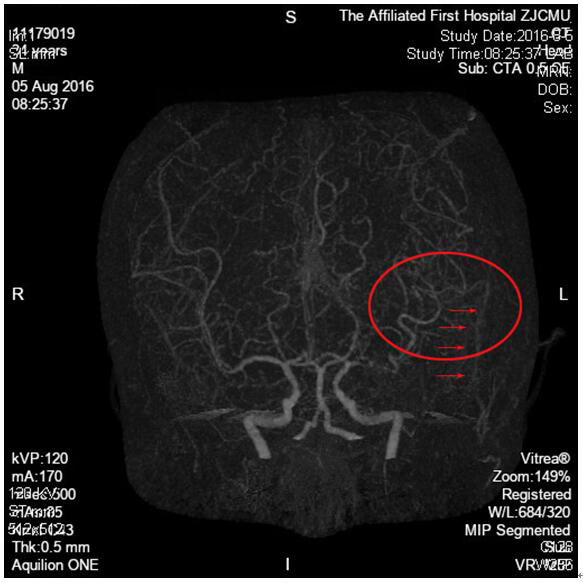

术后1周,CT血管成像显示:左侧近端闭塞,但远端已经显影,吻合血管通畅(小箭头处)。